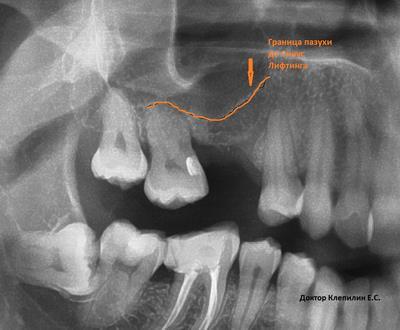

Что такое синус-лифтинг и зачем его проводят? Синус-лифтинг это вспомогательная операция при установке имплантатов. Для установки имплантатов нужны хорошие условия и в первую очередь это объем костной ткани в которую устанавливается имплантат. А объема не всегда достаточно. На верхней челюсти, в области жевательных зубов хирурга ограничивает гайморова пазуха. Когда расстояние до пазухи совсем мало, всего несколько миллиметров, применяют методику синус-лифтинга. Дно гайморовой пазухи приподнимают, проводят костную пластику и устанавливают имплантат. Операция требует высокой квалификации хирурга-стоматолога, надежных материалов и качественного инструментария.